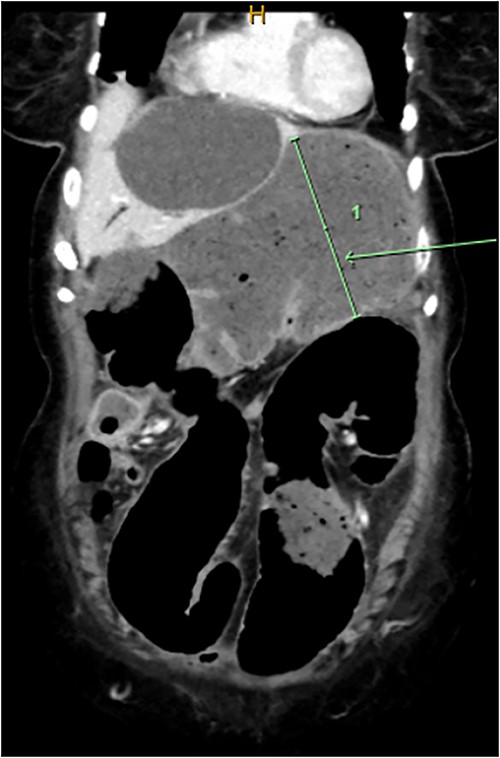

Computed tomography on current presentation demonstrated a mechanical LBO with a transition point at the anastomosis, with significant large bowel dilatation (see Figs 1 and 2). Flexible sigmoidoscopy revealed severe luminal narrowing at the anastomosis 20 cm from the anal verge prohibiting scope progression, with intra-luminal purulent discharge. She underwent a laparotomy and Hartmann’s procedure, with findings of severe colorectal anastomotic stenosis and a small, localized perforation. The colon proximal to the stricture was dilated but viable, with a caecal diameter of approximately 20 cm (see Figs 3 and 4). Histopathology confirmed a benign stricture with extensive fibrosis and a segment of full thickness necrosis and perforation. There was no evidence of malignancy and the post-operative recovery was unremarkable.

Intra-operative findings, viable but severely dilated caecum and proximal colon.